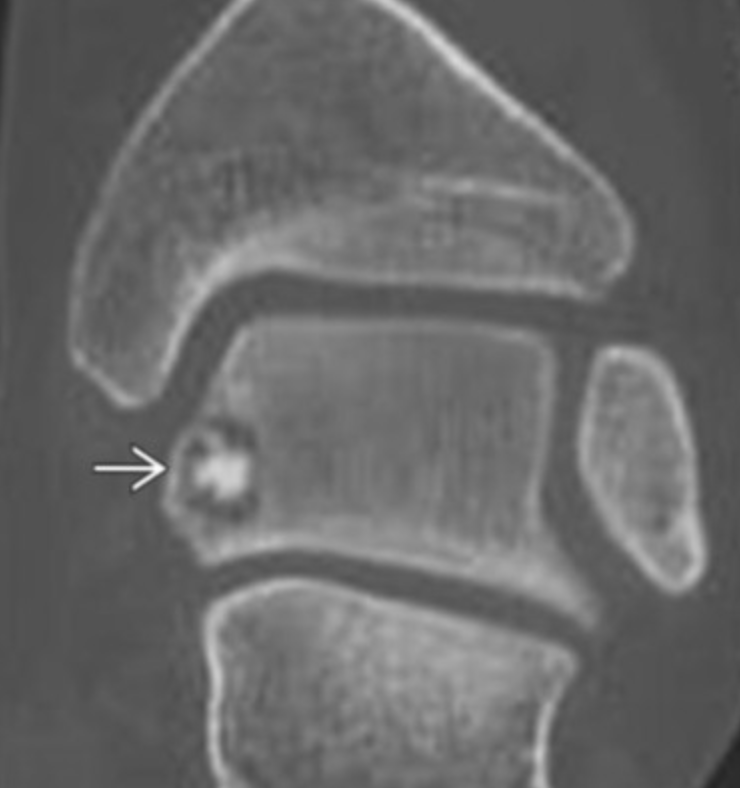

Osteoid Osteoma

• Basically looks like a target

• Central sclerotic area with peripheral lucency

• Hot on bone scan